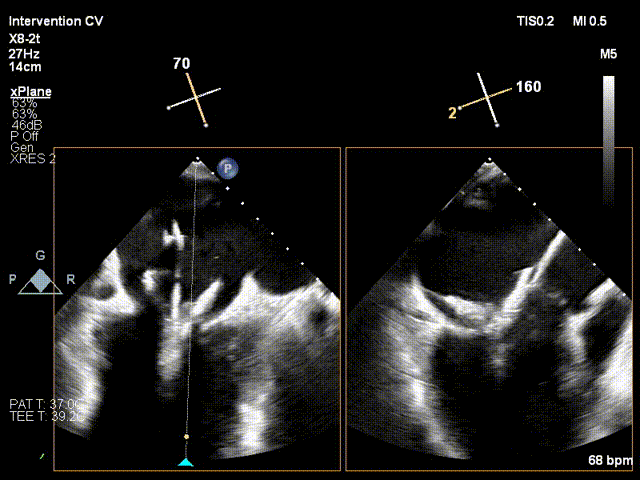

手术采用左侧第五肋间微创切口入路,超声引导下经心尖将导丝置入左房,送入瓣膜输送系统,经过一系列超声定位后逐渐释放瓣膜。确认瓣膜位置满意后撤出输送系统,瓣架恢复膨胀完全、锚定良好,人工二尖瓣瓣叶形态完好,无反流及无瓣周漏,人工二尖瓣峰值流速1.10m/s、平均压差2mmHg,峰值压差5mmHg,由连续多普勒据PHT估测面积约3.5cm²,左室流出道无梗阻,峰值流速0.76m/s。术中出血约100ml,无输血,术后患者安全返回监护室。

TMVR术前

TMVR术中